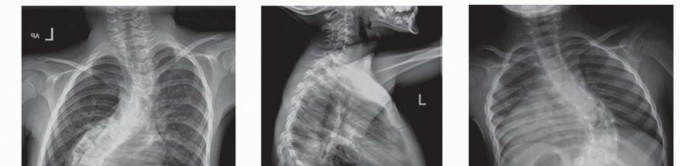

Growing Rod Instrumentation for Early-Onset Scoliosis DEFINITION Early-onset scoliosis (EOS) is defined by th…